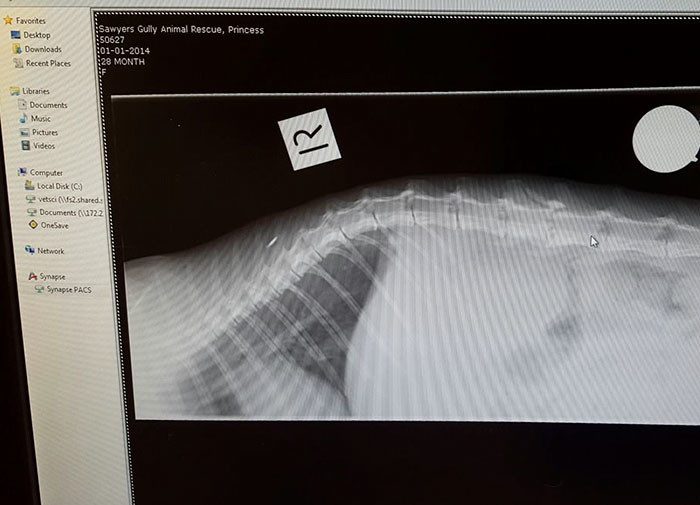

Мужчина, живущий на участке, предположительно схватил кошку за хвост и ударил ее об автоприцеп. Группе зоозащитников показалось, что кошка мертва, так что они подобрали лишь ее котят в возрасте 1 месяца. Тем не менее, на следующий день произошло невероятное: кошка поползла, используя лишь передние лапы, прямо к своим детям!

Вот что значит Австралия, какое там отношение, медицина, снимок хвостика сделали, котят в одеялко. А у нас и кошку и котят бы в мусорку выбросили и дальше пошли, а зачем возиться? Когда наша кошка не могла дышать, ей даже в ветклинике не оказали должной помощи и она умерла у меня на руках. Да что коты… к людям такое отношение. Поэтому хоть и принято сейчас ругать заграницу, но внимательного отношения к жизни у них не отнимешь и как-то никто не возвращался до сих пор оттуда…